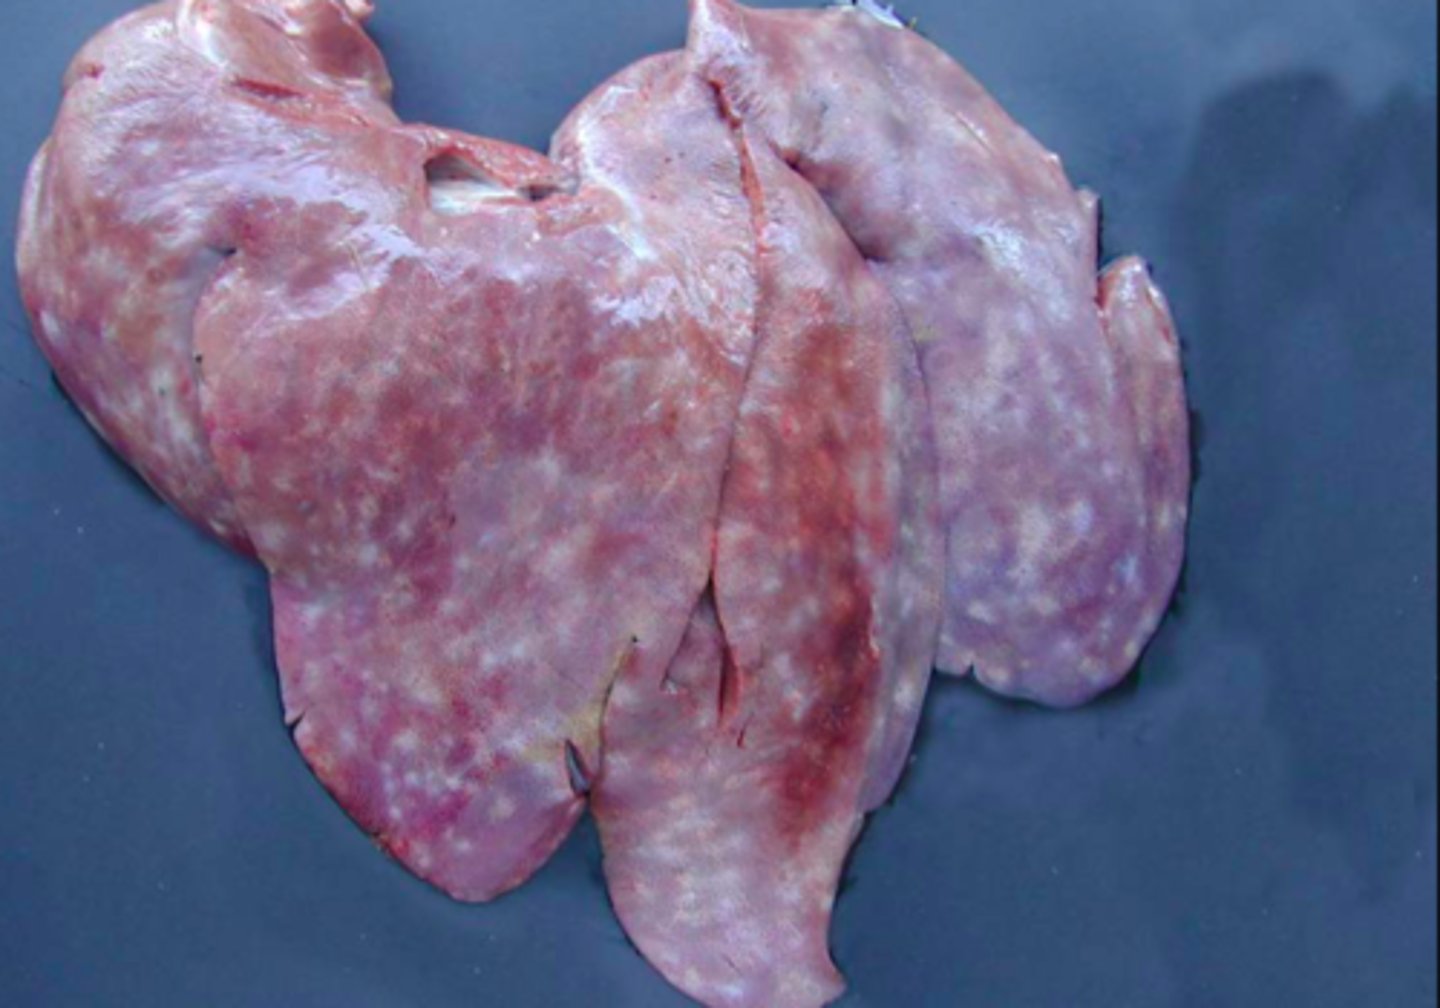

Kronisk multifokal, fibrøs, interstitiel hepatitis

Ætiologi: migration af Ascaris suum larver

Lever fra svin, hvad er den patoanatomiske diagnose og ætiologien?

Kronisk multifokal, fibrøs, interstitiel hepatitis

Ætiologi: migration af Ascaris suum larver

Lever fra svin, hvad er den patoanatomiske diagnose og ætiologien?